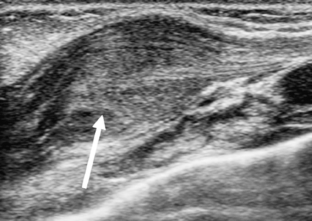

A 17-month-old boy presented with a palpable anterior chest wall mass and was evaluated by chest radiography, sonography, and MRI. No history of trauma was provided initially. Sonography and MRI showed a costal cartilage fracture with overlying hematoma. Identification of a fracture isolated to the costal cartilage is rare and this is a unique case among children. In the appropriate clinical setting, costal cartilage fractures can be confirmed by sonography alone, and follow-up assessment can be based on clinical evaluation without the need for additional cross-sectional imaging.

Fig. 2